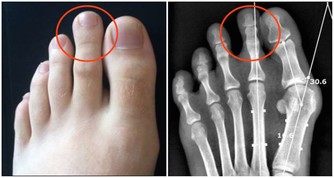

空鼻症到底是什麼?即過分的鼻甲切除性手術導致的鼻腔黏膜萎縮及一系列伴發症狀。

天津醫科大學第二醫院耳鼻喉科主任醫師黃永望曾說:

“患者一般是之前患有慢性鼻炎、鼻息肉、鼻竇炎等鼻部病症,想通過手術通暢鼻腔,

但手術後感覺還是不夠通暢或者過度通暢,部分患者就成了空鼻症。”